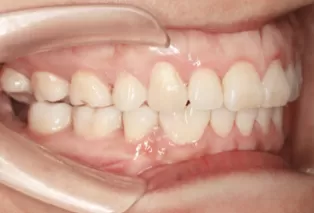

Intraoral photos